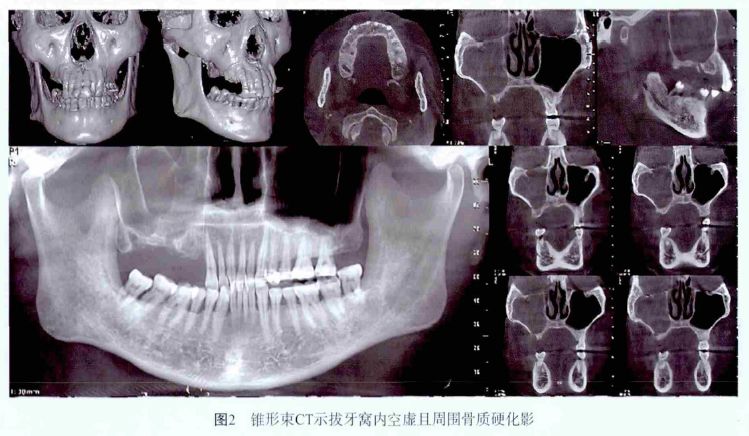

锥形束CT 示拔牙窝内空虚,周围骨质硬化影,提示骨质有破坏( 图2) 。结合患者病史诊断为:BONJ。